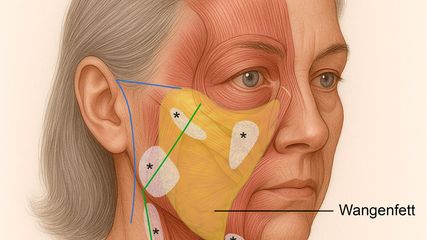

Moderne Faceliftchirurgie

Das Facelift, eine klassische Operation der plastischen Chirurgie, erfährt in den letzten Jahren ein Revival. Die gestiegene Nachfrage der Patienten ist einerseits auf bessere Ergebnisse ...